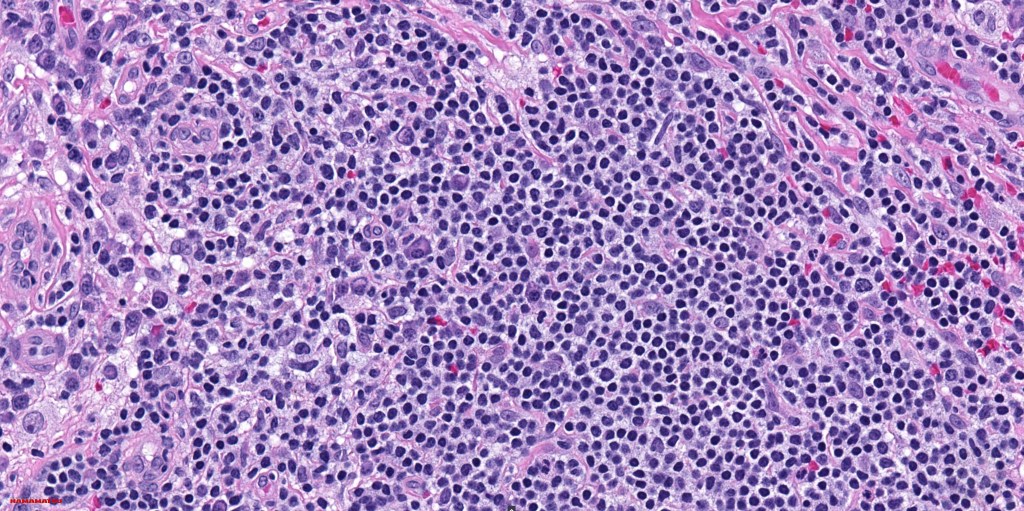

•Histiocytes are large with irregular borders and abundant cytoplasm

• Vesicular nuclei with a prominent nucleoli

•Emperipolesis of lymphocytes, plasma cells & neutrophils

•Lymphoid follicles with germinal centers sometimes present